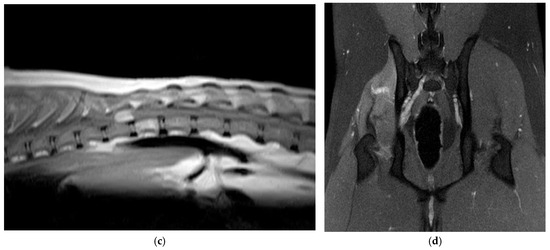

Canine Hemangioblastoma: Case Series and Literature Review

by Çağla Aytaş, Alberto Cauduro, Cristian Falzone, Stefania Gianni, Anna Tomba and Carlo Cantile

Human hemangioblastoma is a benign, slow-growing, highly vascular neoplasm. The tumor most commonly arises in the cerebral hemispheres and cerebellum, where it is more frequently observed in patients with von Hippel–Lindau disease. In veterinary medicine, hemangioblastoma has only been described in the central [...] Read more.

Human hemangioblastoma is a benign, slow-growing, highly vascular neoplasm. The tumor most commonly arises in the cerebral hemispheres and cerebellum, where it is more frequently observed in patients with von Hippel–Lindau disease. In veterinary medicine, hemangioblastoma has only been described in the central nervous system of dogs and in the skin of lambs. Our study aimed to characterize the clinical and neuropathological features of five cases of canine spinal cord hemangioblastoma and one case of sciatic nerve localization, and to compare these results with those reported in the veterinary literature. Diagnoses were achieved by neurological examination, neuroimaging, surgery or post-mortem examination, histopathology, and immunohistochemistry. All tumors were composed of numerous, haphazardly arranged capillaries lined by plump endothelium and interstitial fusiform to stellate stromal cells. Immunohistochemically, the stromal cells were strongly immunolabeled with NSE and carbonic anhydrase IX and were negative for von Willebrand factor VIII and inhibin-α. Canine hemangioblastoma exhibits morphological and immunohistochemical features comparable to the human counterpart, although the latter is mostly positive for inhibin-α. Surgery may be effective in cases of intradural-extramedullary and peripheral nerve locations, as in humans. This is the first report of peripheral nerve hemangioblastoma in animals. Full article

(This article belongs to the Section Veterinary Clinical Studies)

Show Figures

Figure 1